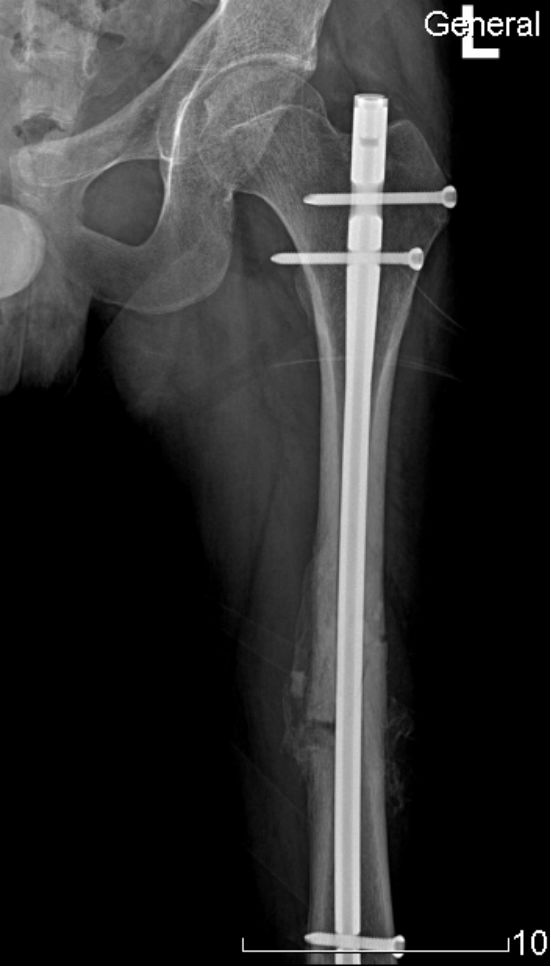

交锁髓内钉有较好的抗旋转、抗压缩作用,固定稳定性好,符合生物学固定原则(BO),在四肢长骨中应用广泛。

股骨粗隆下2cm距膝关节9cm以上的各种类型骨折。

固定骨折的力臂比钢板长,作用力均匀分散在整个骨干的中轴上,不易发生折弯变形。

锁钉使骨干从上到下形成一体,防止缩短和旋转,对骨折的固定达到最大的稳定性。